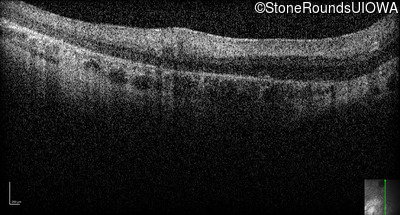

Optical Coherence Tomography - Right -

No Light Perception

Exemplar

Expanded OCT Stack

×